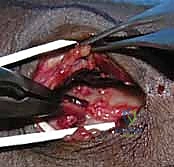

2. الشق الجراحي والوصول للعظم (Surgical Approach)

يقوم الدكتور هطيف بعمل شق جراحي دقيق (غالباً من الجهة الأمامية للرسغ - Volar Approach). يتم إبعاد الأوتار والأعصاب (مثل العصب الأوسط) والأوعية الدموية بمنتهى الحذر باستخدام تقنيات الجراحة المجهرية لحمايتها من أي ضرر.

3. قص العظم التصحيحي (The Osteotomy)

بناءً على التخطيط الثلاثي الأبعاد المسبق، يستخدم الدكتور هطيف مناشير عظمية دقيقة جداً لعمل شق في العظم في نقطة التشوه الأصلية. يتم فتح العظم وتعديل زاويته واستعادة طوله الطبيعي.